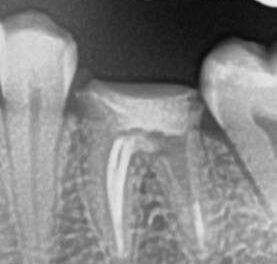

Специализация: терапия(эндодонтия), ортопедия, имплантология.